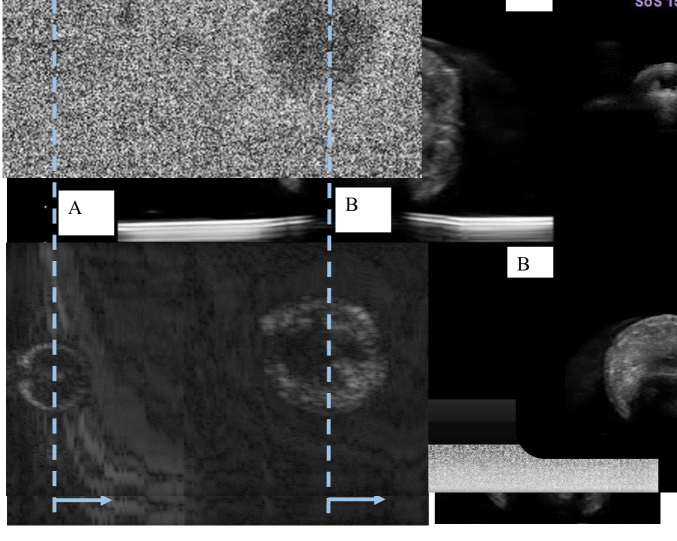

To transform the captured RF data into B-mode images, a process was employed that involved taking the magnitude of the analytic signal derived from the RF data using the Hilbert transform and then displaying it in a logarithmic scale. A representative sample of the captured RF data and the resulting B-mode image can be found in Fig. 8. This entire process was repeated for ten individual trials to ensure a comprehensive assessment of the system’s performance.

We conducted 20 trials on the grape phantom for testing the system efficiency. Each trial started from a different target lesion position and a robot configuration. Our system achieved a success rate in automated image acquisition. The overall procedure took around 1 to 2 minutes on average, which indicates a high efficiency of our co-robotic US interface. A representative X-ray image and the corresponding C-section obtained by slicing the US 3D volume is illustrated in Fig. 10. The actual US images of the two lesions at a specified cross section are displayed in the lower right of the figure.

We computed the averaged CNR across one X-ray and 171 US images in a volume scanning that contains two simulated lesions (grape and blueberry). The respective CNR values for the X-ray and US images are presented in Fig. 10. Specifically, the CNR for the grape is 264.12 in the ultrasound and 0.46 in the X-ray, while for the blueberry, the CNR values are 81.81 in ultrasound and 0.20 in X-ray.